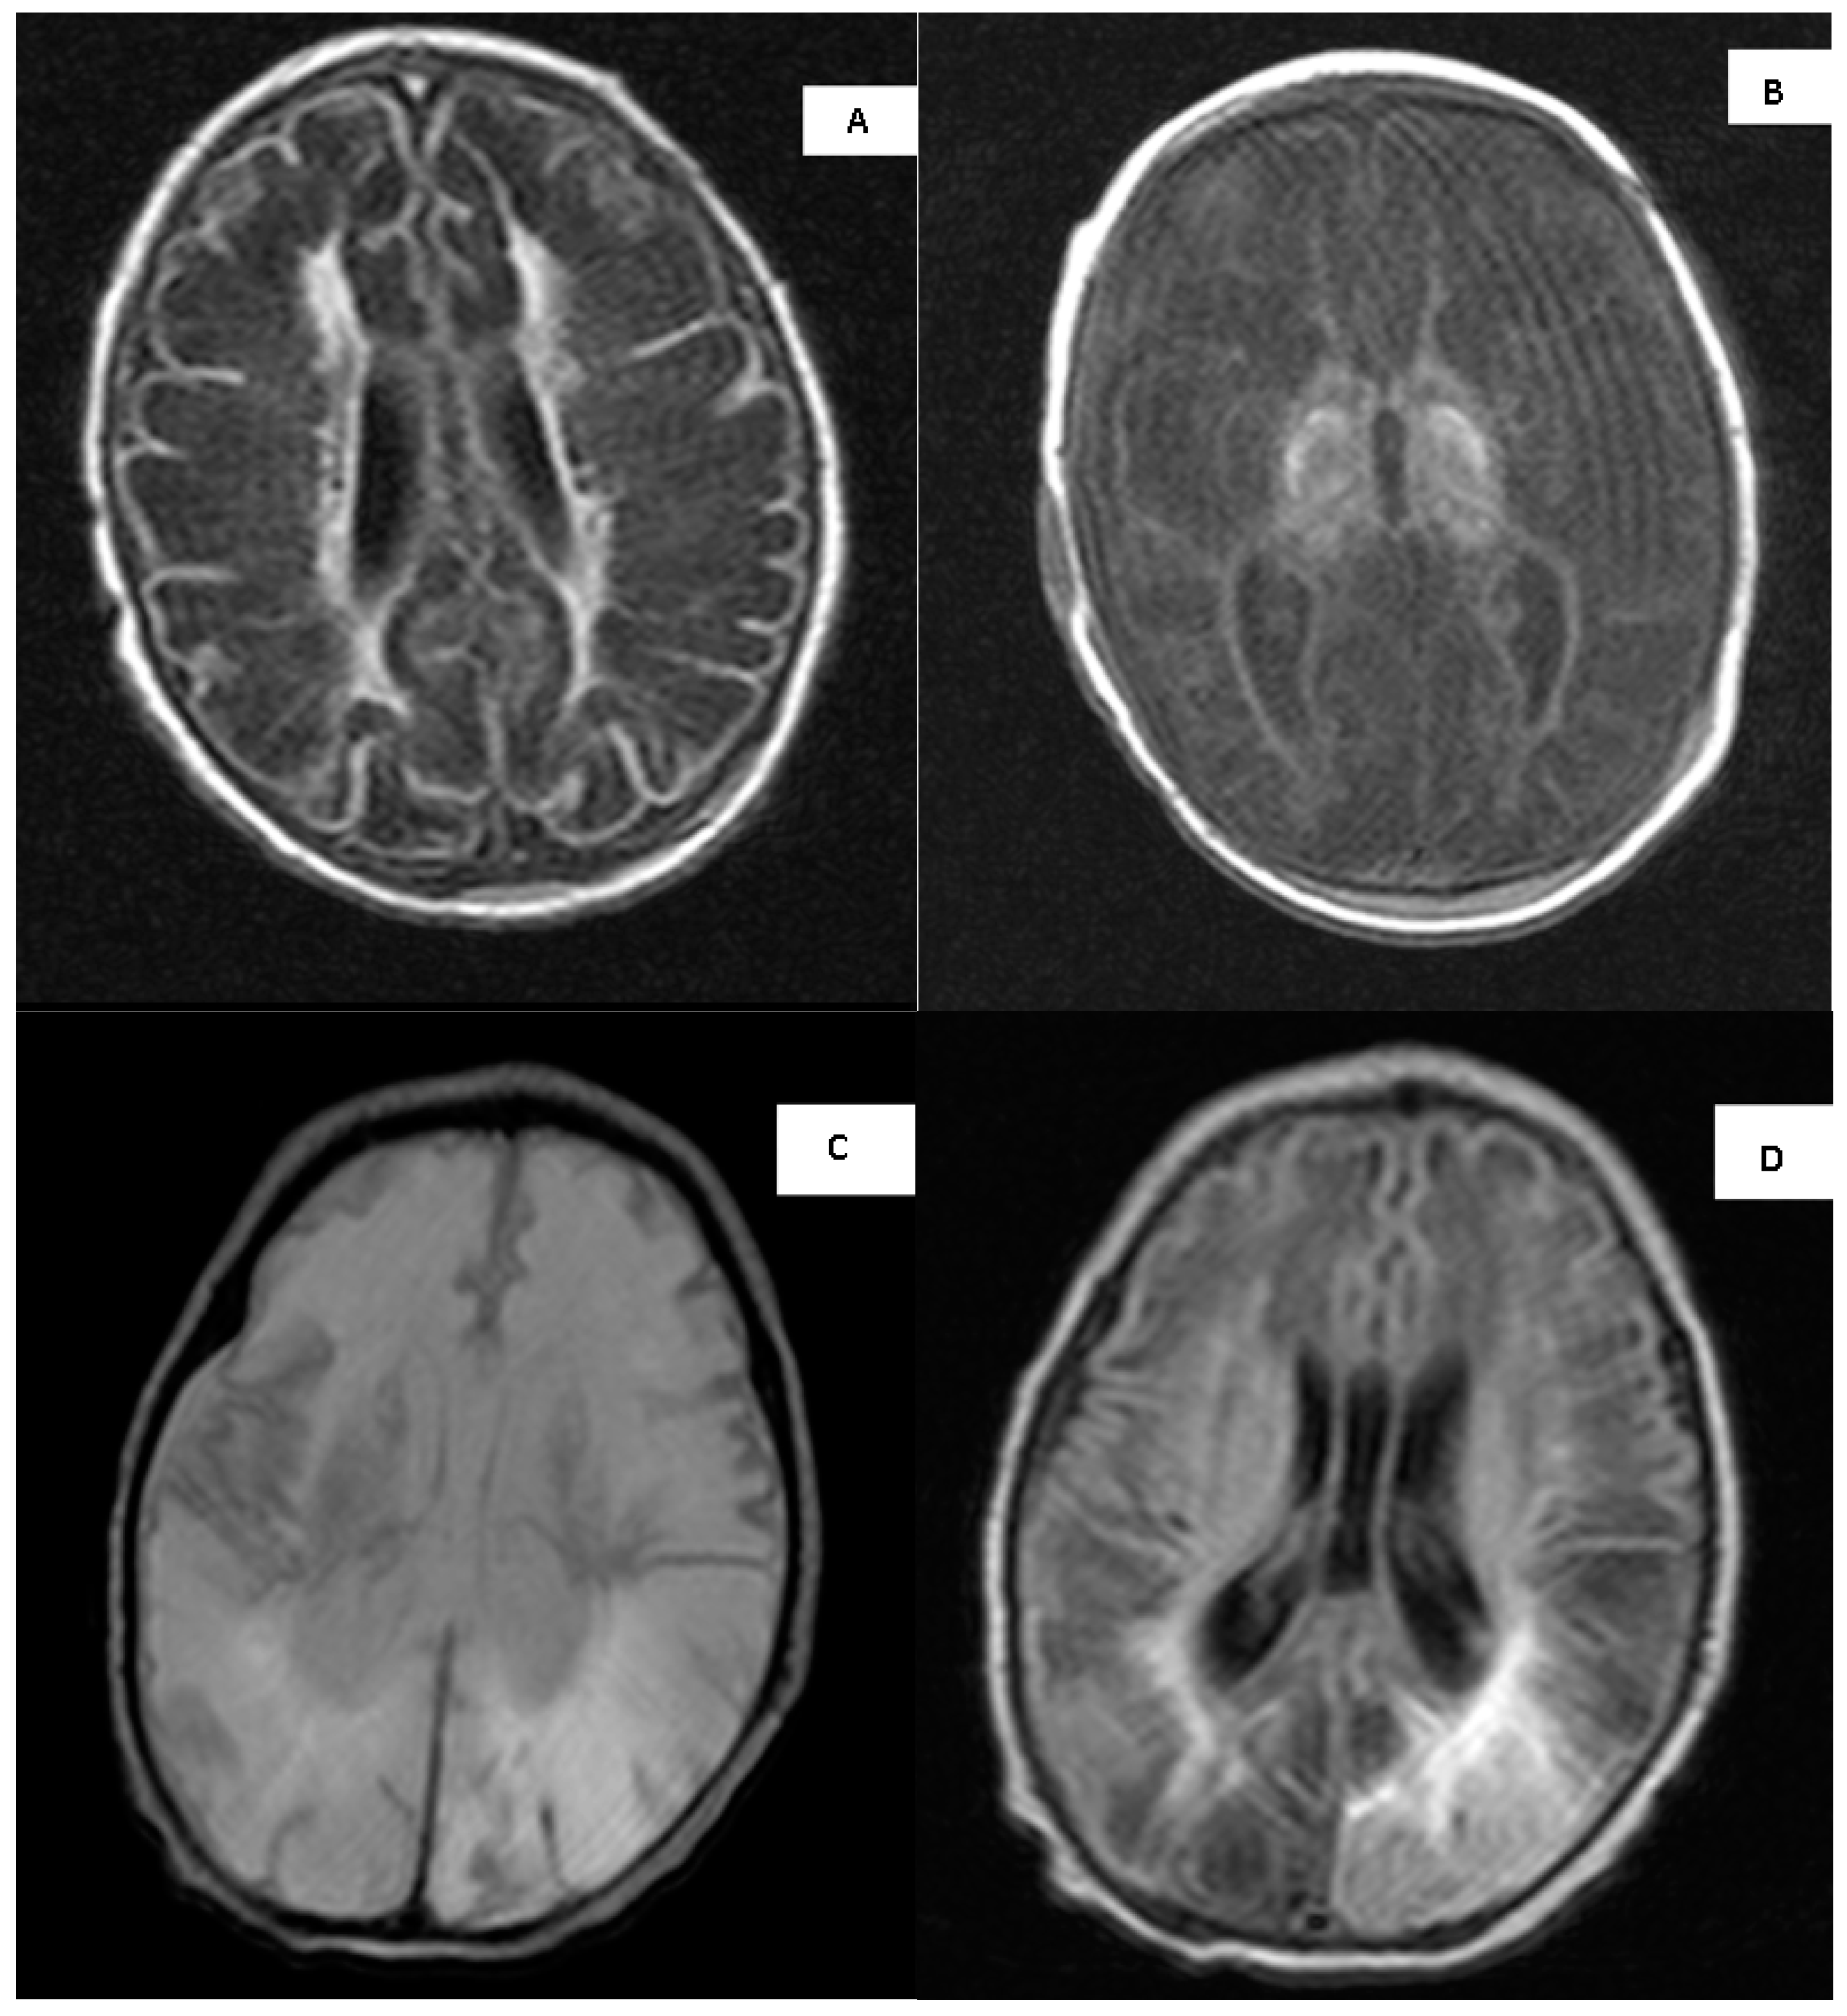

3.10. MRI Imaging

- Barkovich, A.J.; Miller, S.P.; Bartha, A.; Newton, N.; Hamrick, S.E.G.; Mukherjee, P.; Glenn, O.A.; Xu, D.; Partridge, J.C.; Ferriero, D.M.; et al. MR Imaging, MR Spectroscopy, and Diffusion Tensor Imaging of Sequential Studies in Neonates with Encephalopathy. Am. J. Neuroradiol. 2006, 27, 533–547. [Google Scholar]

- Barkovich, A.J.; Hajnal, B.L.; Vigneron, D.; Sola, A.; Partridge, J.C.; Allen, F.; Ferriero, D.M. Prediction of Neuromotor Outcome in Perinatal Asphyxia: Evaluation of MR Scoring Systems. Am. J. Neuroradiol. 1998, 19, 143–149. [Google Scholar] [PubMed]